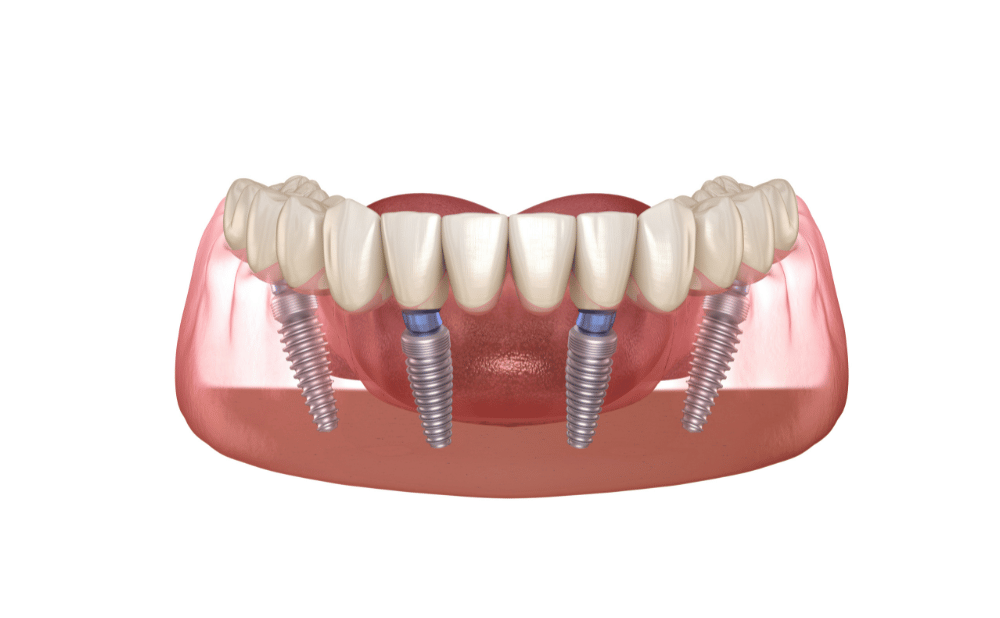

オールオンフォーは、最小4本の人工歯根を顎の骨に固定する構造のため、噛む力は天然歯の約80%ほどまで回復します。

また、天然歯と見分けがつかないほど、審美性の高い素材を使用します。

総入れ歯と大きく違う点は、口の中に厚い土台がないことで口元のハリが保たれ、自然な笑顔を取り戻せます。

オールオンフォーは、噛んだときの力が人工歯根に伝わり、天然の歯と同じように顎の骨に適切な刺激が伝わります。

刺激が伝わることで、顎の骨が痩せるのを防ぎます。